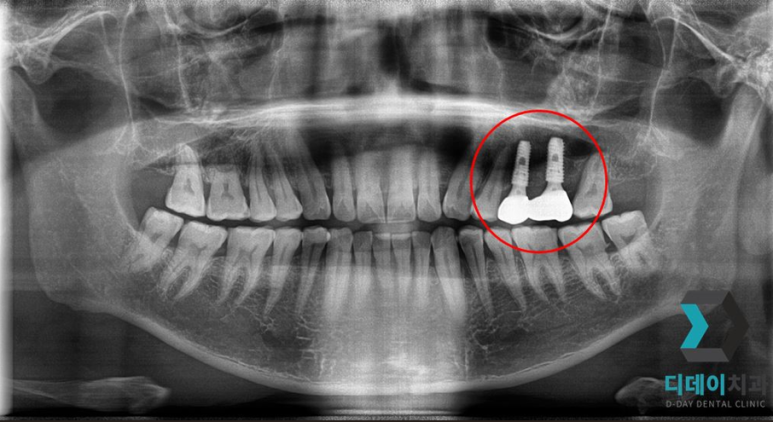

<전 2021-12-28>

<후 2022-08-06>